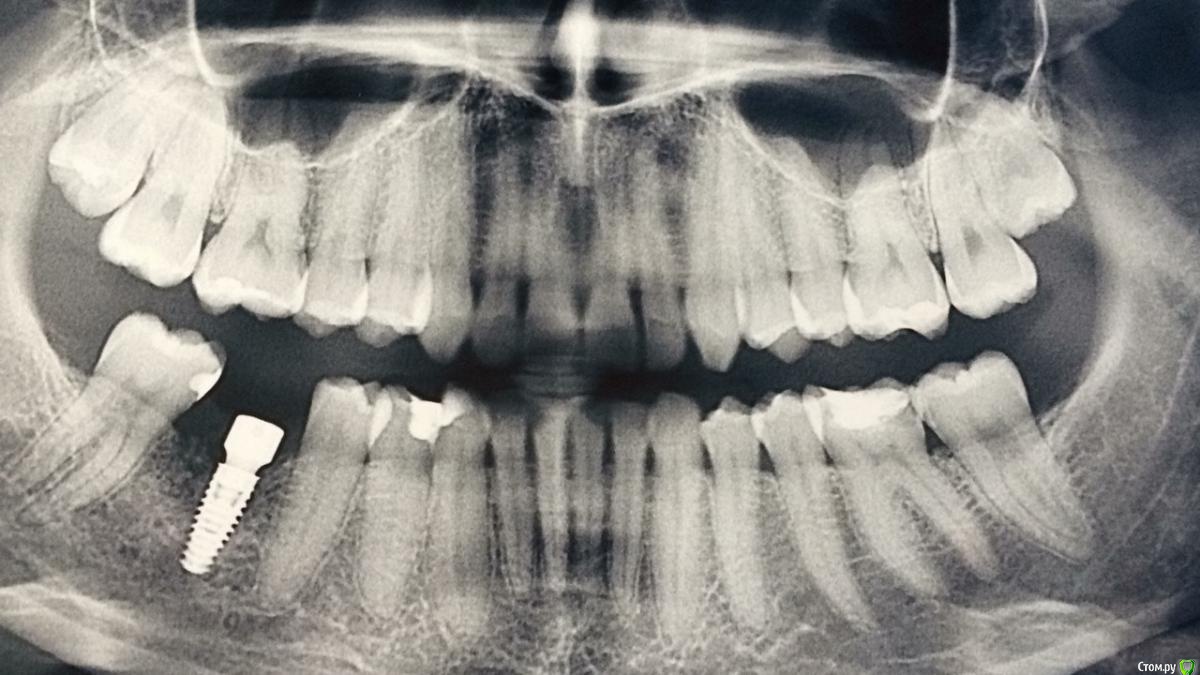

hogsmeed Опубликовано 7 марта, 2018 Поделиться Опубликовано 7 марта, 2018 По снимку вроде все ок, а почему вы не можете довериться врачу своему? Ссылка на комментарий

flyfli Опубликовано 7 марта, 2018 Автор Поделиться Опубликовано 7 марта, 2018 подскажите, по снимку там все ок Вы сказали, Вы бы пустили такого пациента уже к ортопеду? Сколько можно вообще тянуть этот момент и ходить с формирователем , ничего если мес 5 где-то получается? Ссылка на комментарий

Vitasem Опубликовано 18 марта, 2018 Поделиться Опубликовано 18 марта, 2018 подскажите, по снимку там все ок Вы сказали, Вы бы пустили такого пациента уже к ортопеду? Сколько можно вообще тянуть этот момент и ходить с формирователем , ничего если мес 5 где-то получается?не страшно Ссылка на комментарий